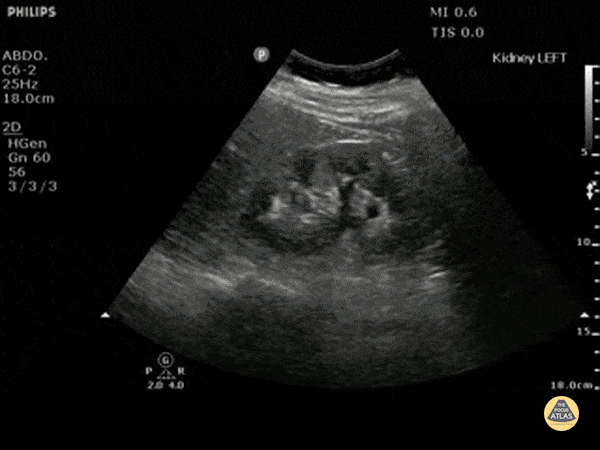

Renal/GU - Moderate Hydronephrosis

Moderate (grade three) hydronephrosis can be appreciated here with dilation of both the renal pelvis and calcyces. The renal cortex is also thinned. There is not gross atrophy. Dr. Justin Bowra et al. (Dr. Yogi)